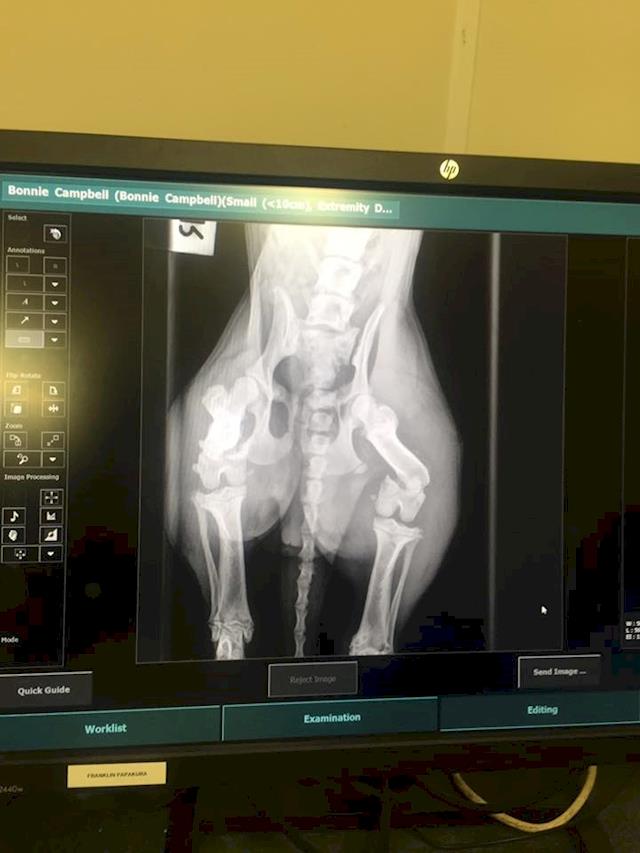

I just found out how to do updates, yay. so here is where little Bonnie is at:

She had her x rays yesterday at the vet, which confirmed that she has two broken Femurs. What the awful thing is that both legs were broken on separate occasions, they are approx 1-2 weeks apart from what they can gather from the x rays and how the first one has tried to repair thus far. Being that one leg is a little older that pushes the cost of the surgery up as they will have to re break the bone and re set it back in the correct place, which can prove to be quite tricky. They are confident that it can be done, it just takes a lot more time which pushes the cost up. The good news is that her hips and pelvis are still perfectly intact with no fractures...phew :)

So Bonnie is now booked in for her surgery early next week, as the surgeon is away until Monday. so she is nice and comfortable on pain medication until then, and she seems alot more bright eyes and happy.